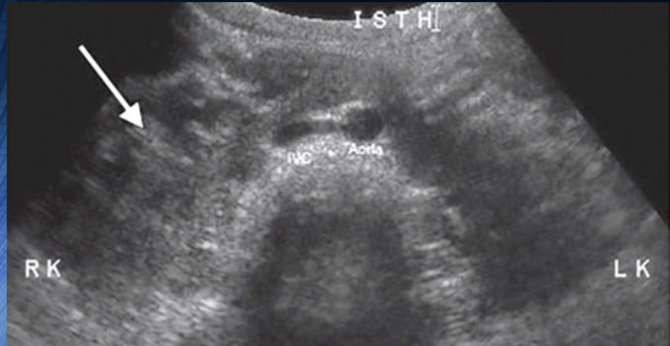

What is this?

Horseshoe Kidney (hard to see on US)